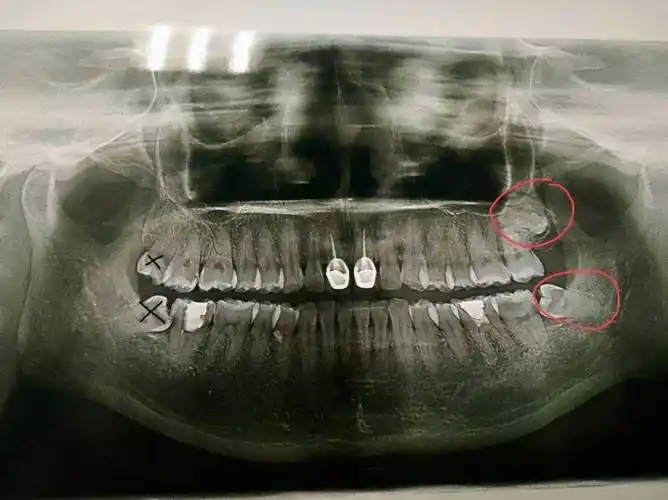

智齿在颌骨内由于位置不当,不能萌出到正常咬合位置,被称为阻生智齿

阻生智齿不同形态示意图

形态不一的下颌阻生智齿,不论啥形态反正都不在正常位置上~#口腔正畸